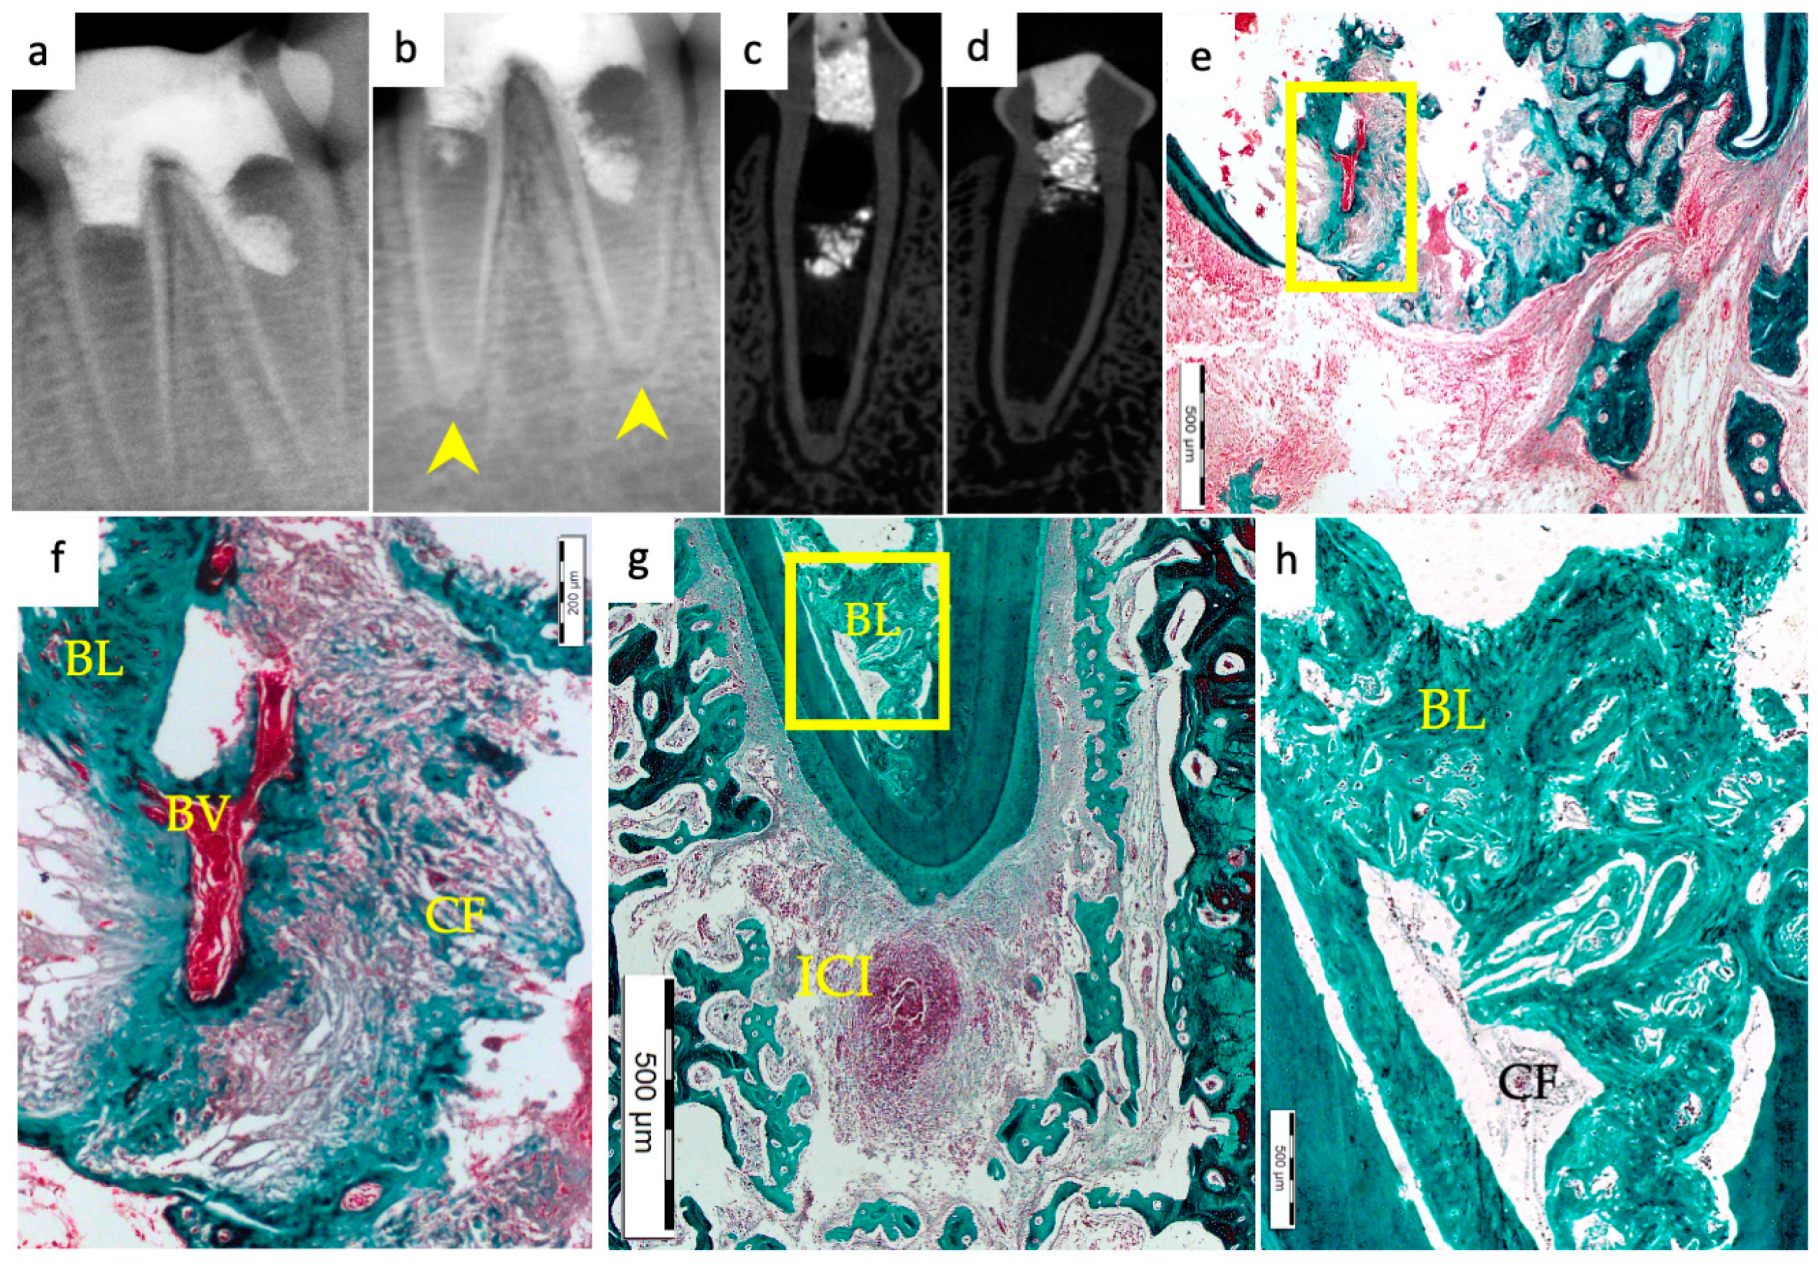

3.1. Hard Tissue Deposition

3.2. Type of Hard Tissue Formed

3.3. Vascularization and Formation of Vascularized Soft Connective Tissue

3.5. Apical Closure

3.6. Positive and Negative Control Groups